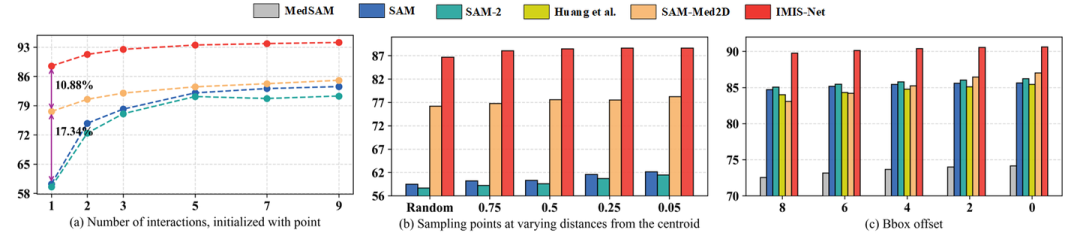

02 交互策略对模型的影响

图5. 不同交互策略对交互式分割模型的性能影响

IMIS-Bench 提供了一个统一的基准框架,对 IMIS-Net 和现有交互式分割方法进行了全面、系统的性能评估。实验表明,IMIS-Net 在多种模态和任务场景下显著超越现有技术。同时,团队还对多种交互策略对分割性能的影响进行了深入研究,为模型的优化和交互设计提供了宝贵的指导。